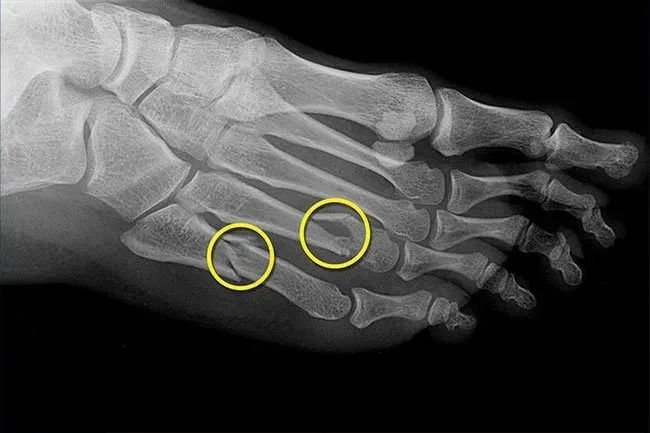

Zlomeniny napětí

U žen mohou hormonální změny, které přicházejí s menopauzou, snížit hustotu kosti (osteoporóza) a usnadnit zlomeniny kostí včetně změn na nohou. Muži mohou také získat více křehkých kostí, jak stárnou. Zlomenina napětí potřebuje k uzdravení několik týdnů odpočinku. Budete chtít posílit své kosti cvičební dietou a možná také léky. Zeptejte se svého lékaře na výhody rizik a co by vám pomohlo nejvíce.